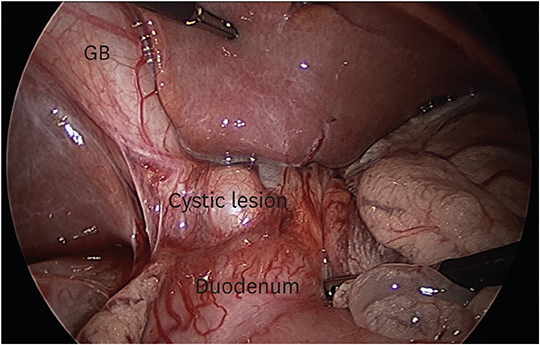

The patient received laparoscopic choledochal cyst excision and Roux-en-Y hepaticojejunostomy. Intraoperatively, the cystic lesion was identified to be a diverticulum emerging from the CD, closely adjacent to the lateral side of the duodenum 1st–2nd portions (Fig. 4). There was major difficulty dissecting the CHD due to severe inflammation around the cyst, and conversion to open surgery was performed. The pathology report identified the excised cyst as a benign cystic lesion of bile duct origin with chronic active inflammation. The patient recovered well and was discharged 3 weeks after surgery without acute complications. She visited the outpatient clinic 1 week after discharge, and there were no significant abnormalities observed.

Fig. 4

Intraoperative laparoscopic view of type II choledochal cyst. The cystic lesion was identified to be a diverticulum emerging from the cystic duct.

GB: gallbladder.